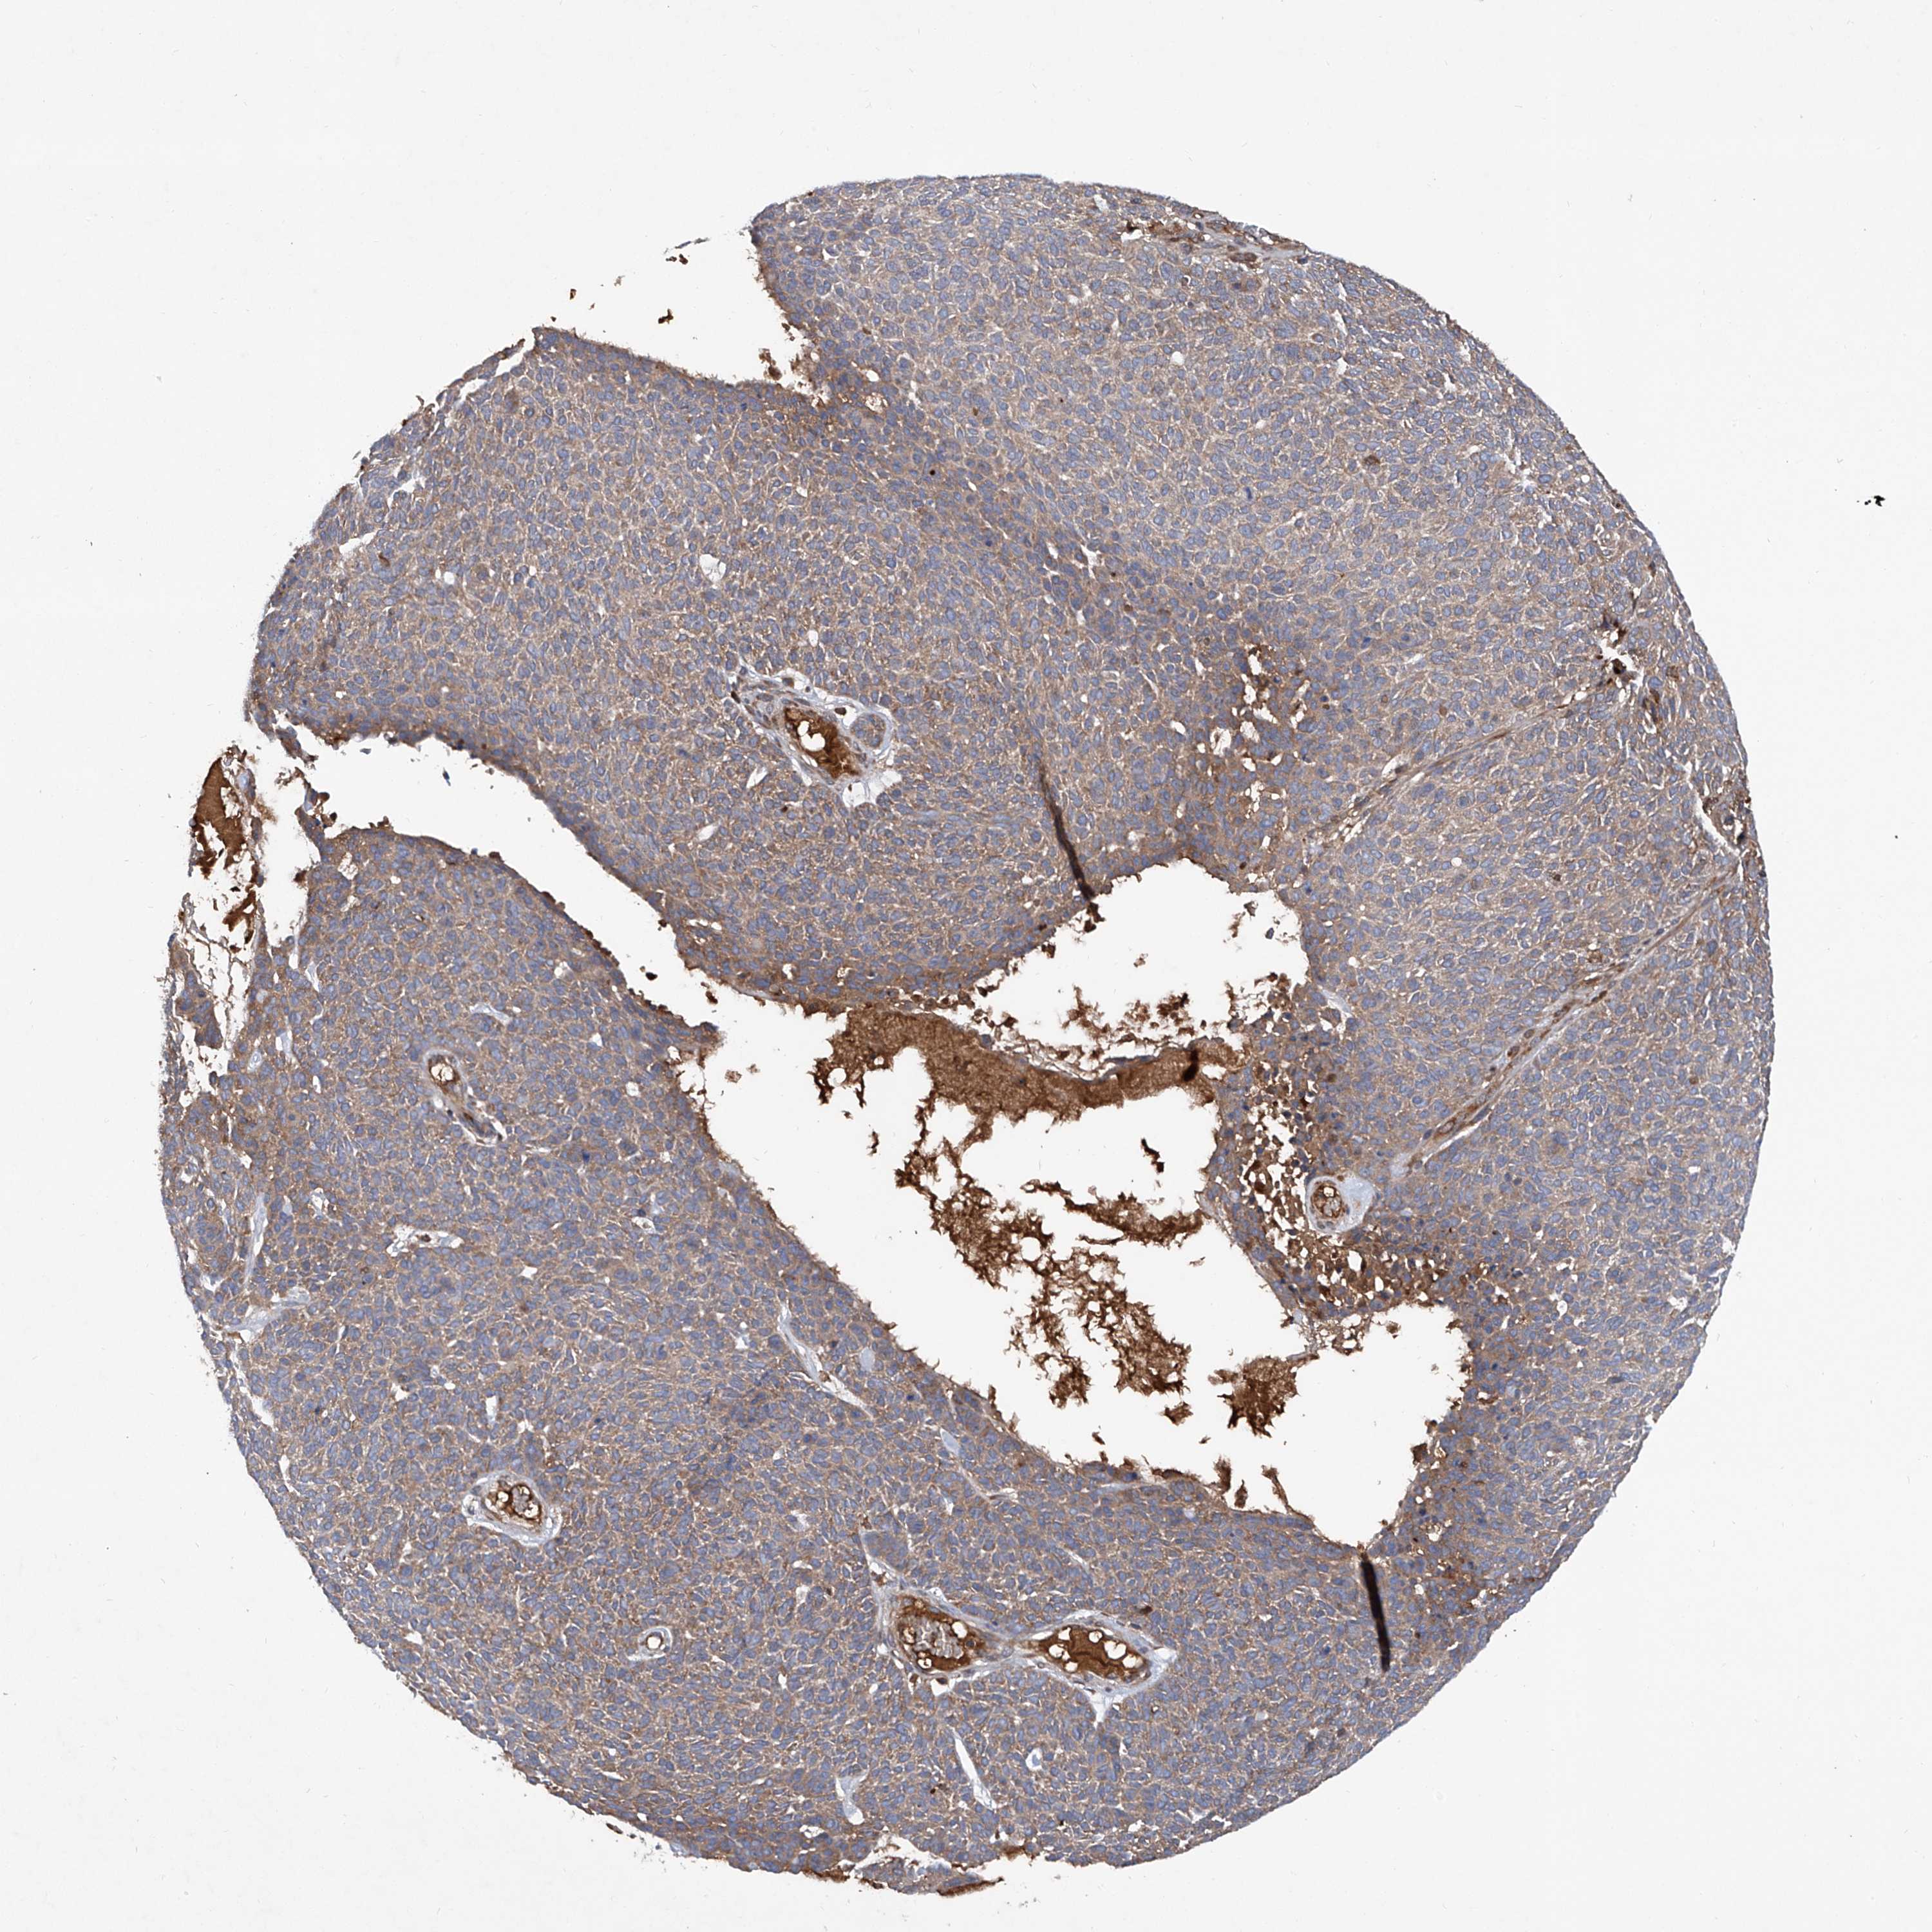

SKIN CANCER - Protein expressioni

A mouse-over function shows sample information and annotation data. Click on an image to view it in a full screen mode. Samples can be filtered based on level of antibody staining by selecting one or several of the following categories: high, medium, low and not detected. The assay and annotation is described here.

Each image is clickable and will lead to virtual microscopy that enables deeper exploration of all samples and also displays staining intensity scores, fraction scores and subcellular localization as well as patient and tissue information for each sample.

Antibody HPA031609

Staining

High

Medium

Low

Not detected

Intensity

Strong

Moderate

Weak

Negative

Quantity

>75%

75%-25%

<25%

None

Location

Nuclear

Cytoplasmic/membranous

Cytoplasmic/membranous,nuclear

Squamous cell carcinoma, NOS

Squamous cell carcinoma, metastatic, NOS